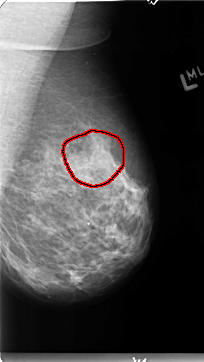

B_3125_1.LEFT_MLO

LEFT_MLO LINES 4704 PIXELS_PER_LINE 2640 BITS_PER_PIXEL 12 RESOLUTION 50 OVERLAY

FILE: B_3125_1.LEFT_MLO.OVERLAY

TOTAL_ABNORMALITIES 1

ABNORMALITY 1

LESION_TYPE CALCIFICATION TYPE PUNCTATE-PLEOMORPHIC DISTRIBUTION CLUSTERED

ASSESSMENT 4

SUBTLETY 2

PATHOLOGY BENIGN

TOTAL_OUTLINES 1

BOUNDARY